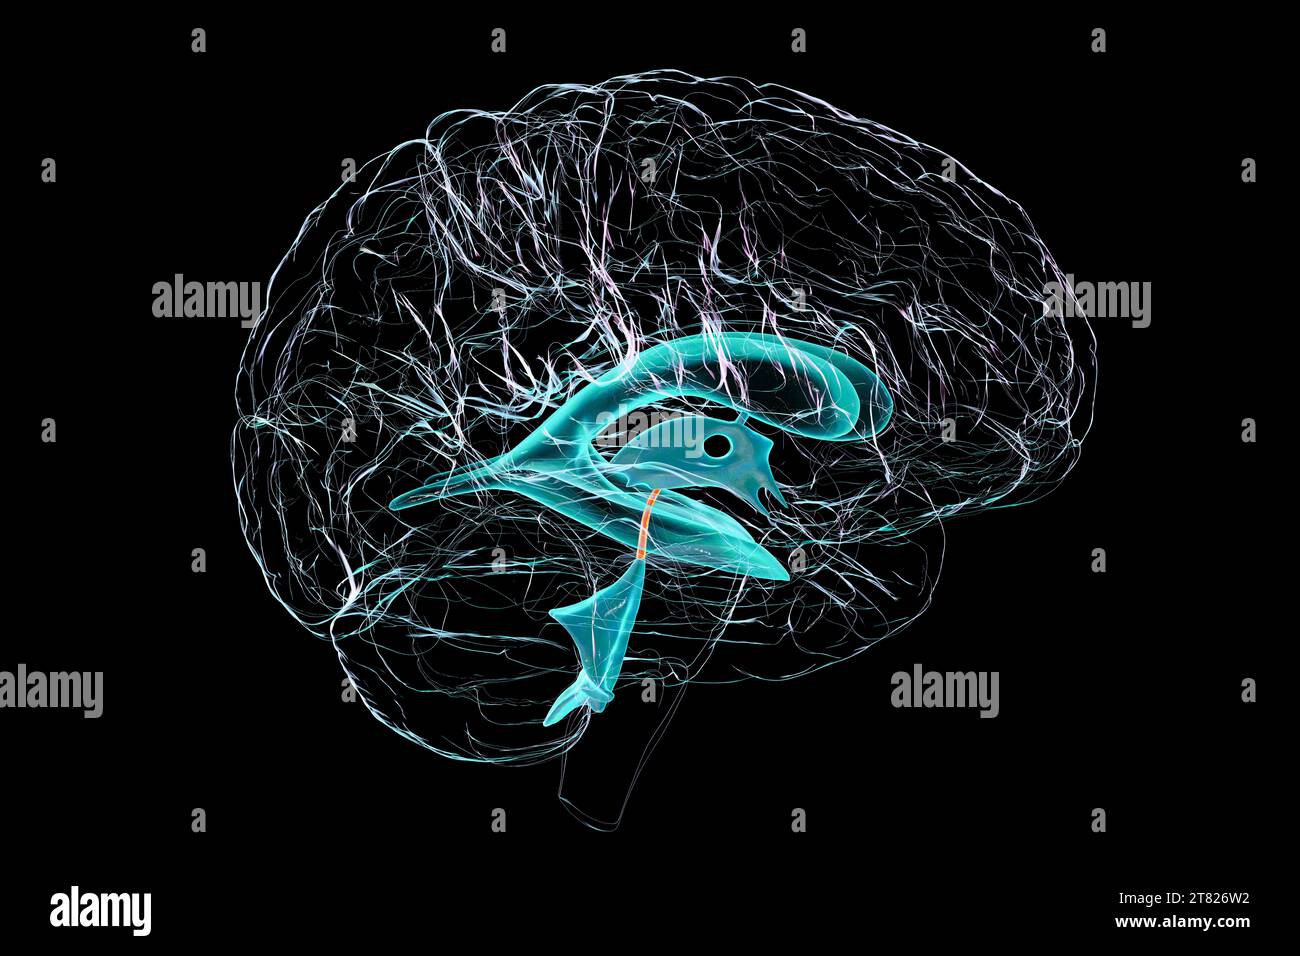

RF2T7NGWH–Ventrikel und zerebrales Aquädukt laterale Röntgenansicht 3D-Rendering-Illustration. Menschliches Gehirn und Ventrikelsystem Anatomie, Medizin, Gesundheitswesen, Scienc

RF2T7NGWK–Ventrikel und zerebraler Aquädukt lateral in Farben Röntgenbild-3D-Rendering-Illustration. Menschliches Gehirn und Ventrikelsystem Anatomie, medizinisch, gesund

RF2T7NGWR–Ventrikel und Hirn-Aquädukt-Röntgenprofil Nahansicht 3D-Rendering-Illustration mit Körperkonturen. Anatomie des menschlichen Gehirns und des Ventrikelsystems,

RF2T7NGWW–Ventrikel und zerebraler Aquädukt in Farben Röntgenprofil Nahansicht 3D-Rendering-Illustration. Anatomie des menschlichen Gehirns und des Ventrikelsystems, medizinisch,

RM2AWFNN9–Menschliche Anatomie, einschließlich Struktur und Entwicklung und praktische Überlegungen d in einem sagittalen mesialen Abschnitt (Abb. 910) wird jede dieser Teilungen als mit einem Teil des Systems der Kommunikation von Räumen verwandt angesehen, die als die dritten Ventrikel des Lateralands, der Aquädukt von Sylvius und der vierte Ventrikel die oben genannten Gehirnhemisphären ausdehnen. Durch den Hirnstamm und unter dem Kleinhirn bis zum zentralen Kanal des Rückenmarks. Da die lateralen Ventrikel zwei innumerieren, ist die Theirstellung im Zusammenhang mit den Gehirnhemisphären, in denen sie liegen, lateral zum m

RM2AN4TWY–Handbuch der allgemeinen, beschreibenden und pathologische Anatomie (Band 2). Ventrikel, ein. Ventrikel des Kleinhirns, b. Aquädukt von Sylvius, C. Dritten Ventrikel, d. Lateralen Ventrikel, 1. Vordere Horn, 2. Hintere Horn, 3. Absteigend Horn, II. Textur, III. Gewicht, IV. Konsistenz, Kap. Iii. Umhüllt des Gehirns. Abt. Ich. Pia - mater, I. des Rückenmarks, II. Von Hirn, ein. - Externe Pia mater, b. Interne pia-mater, ich. Choroid Plexus des vierten Ventrikel, ii. Choroid Plexus des Großhirns, Art.ii.Apert-syndrom Membran, Art. hi. Dura-mater, I. spinalen Dura-mater, II. Zerebrale Dura-mater

RM2CDFE0C–. Elemente der physiologischen Psychologie; eine Abhandlung über die Aktivitäten und die Natur des Geistes, aus der physischen und experimentellen Gesichtspunkten. ide,die corpora quadrigemina. Die Kavität des Neuralrohres bleibt hier klein und bildet das Aquädukt, das den Viertmit dem dritten Ventrikel verbindet. Im Zwischenhirn dehnt sich das Aquädukt in den dritten Ventrikel aus; und hier wird wieder die dorsale Wand des Tubus zu einer breiten, dünnen Membran, die in den Ventrikel gefaltet und Blutgefäße mit sich trägt. Während die zerebralen Hemisphären ihr enormes Wachstum durchlaufen, dehnt sich die Kavität mit ihnen aus, andrema